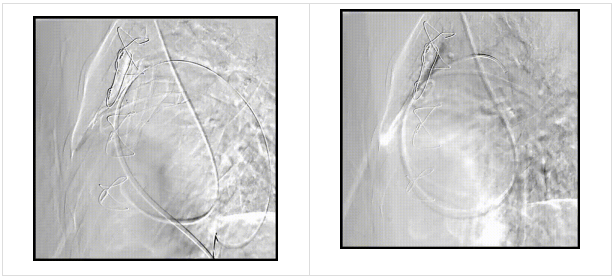

术前造影

术后造影